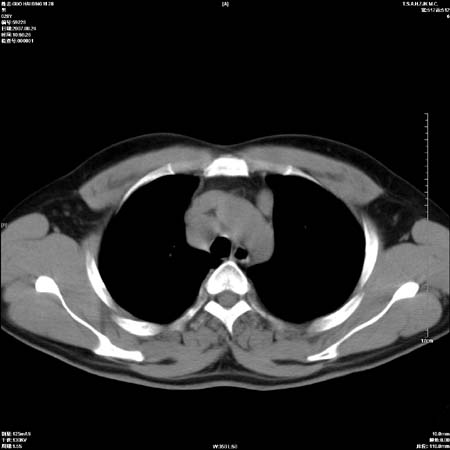

男性,28岁,体检发现左肺病变,患者只有背部隐痛感,哀哉,真不忍心下诊断啊。

左肺门区软组织肿块,左肺上叶支气管开口消失,纵隔内见肿大淋巴结,考虑左中心型肺部,可以做纤支镜取病理确认.

左肺肺门区肿块影,分叶明显:诊断肺癌应该没有疑问。

左肺肺门区肿块影,分叶明显,左肺上叶支气管开口受压,纵隔内见肿大淋巴结,考虑左中心型肺癌。

支持左上叶中央型肺癌伴纵隔淋巴结转移.

左上叶中央型肺癌伴纵隔淋巴结转移

左侧肺门区见一块状病灶可见分叶,纵隔内及左肺门见肿大淋巴结,应该是周围型肺癌而不是中心型肺癌,原因有以下2点,1未见阻塞肺气肿和阻塞性炎症,这么大肿块如果是中心型肺癌就是未分化型或小细胞型肺癌不出现阻塞性肺不张也应该有阻塞炎症或阻塞性肺气肿,2如果是中心型肺癌临床出现最早的症状是咳嗽(此时可无任何异常影象),而此人这么大肿块只有背部隐痛是体检才发现无法解释.

肿块形态影像支持左上叶中央型肺癌伴纵隔淋巴结转移。

直接下肺癌诊断还太早,病灶较大,估计5cm以上,但阻塞性改变及对临近纵隔及支气管侵犯不明显,密度较均匀,弓旁见一单个淋巴结,需要排除炎症性肿块及腺瘤,平滑肌瘤等。

左肺中心型肺癌并纵隔淋巴结转移!考虑为小细胞肺癌,没有手术机会了,只能进行放化了,疗效不错,但极易复发。没办法,现在肿瘤年轻化越来越明显了。